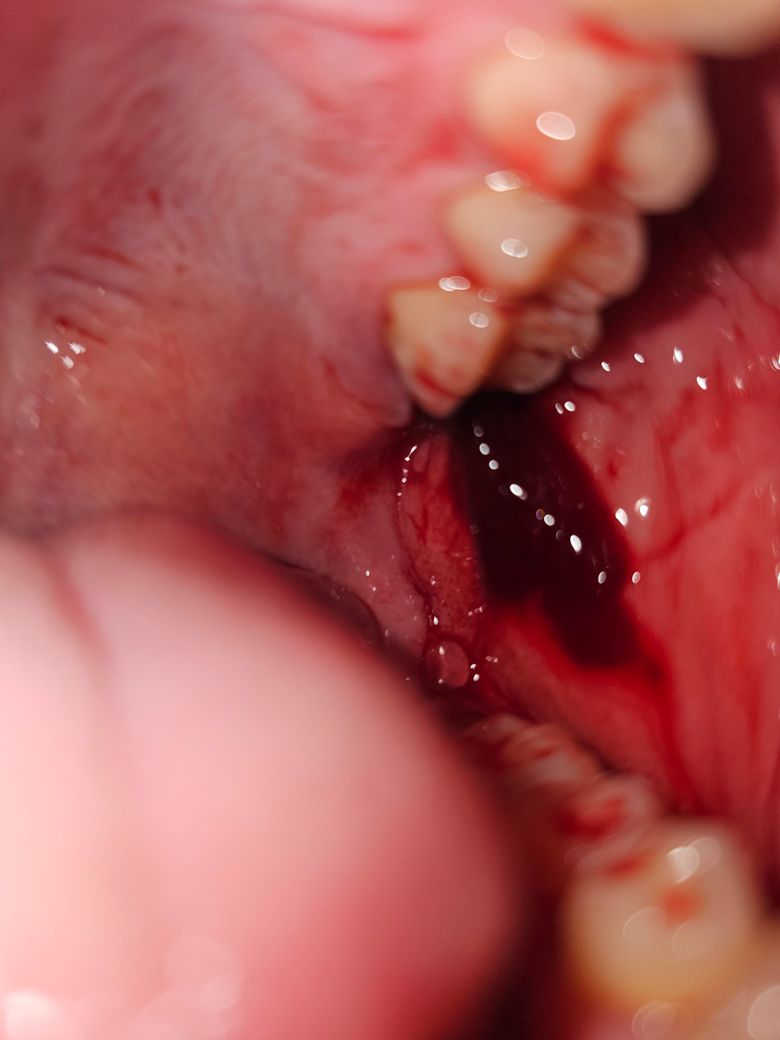

위쪽 어금니 발치 후에 해당 부위에서 젤리 같은 게 밑으로 늘어짐

위쪽 안쪽 어금니를 발치 했고 거즈로 2시간 반쯤 꽉 물고있다가 피 더 안나오는 거 같아서 빼고 한숨 잤는데요.

일어나니까 이쪽에 이질감이 있어 카메라 비추니 저렇게 젤리 같은 게 있었습니다. 아래쪽 발치 할 때는 한번도 못봤는데 검색해보니 혈병인 거 같더라고요.

질문은 이게 제가 아무것도 안했는데도 위에서 덜렁이면서 떨어지는 거 같고 침 삼킬때 동시에 삼켜지는 거 같은데 괜찮은 건가요?

현재 사진상 혈병이 생긴것으로 보이며, 혈병은 발치 부위를 보호하고 치유 과정을 시작하기 위한 자연스러운 방어막 역할을 합니다.

혈병이 일부 작게 떨어져 삼켜지더라도, 발치 부위에 남아 있는 혈병이 상처를 보호하고 치유를 계속 도울 수 있습니다. 첫 24시간 동안 입을 헹구지 말고 발치 부위를 자극하지 않도록 주의하며, 이후 가볍게 소금물이나 소독 가글로 헹구고 부드럽게 양치하길 권합니다.